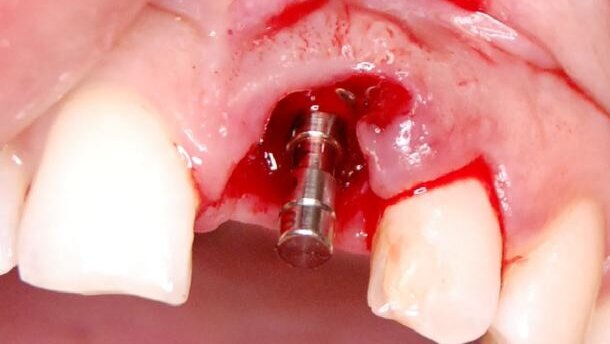

W znieczuleniu nasiękowym Ubistesin Forte (3M ESPE) nacięto ostrzem 15C szczelinę dziąsłową wokół korony zęba 21 oraz dziąsło wokół wydzielającego się przez tkanki fragmentu. Koronę zęba wraz z wkładem usunięto kleszczami, wydzielający się fragment pęsetą, a pozostałą część korzenia wąskim luksatorem (Ryc. 4). Zębodół wyłyżeczkowano i przepłukano 0,5% metronidazolem (Polpharma). W czasie usuwania wydzielającego się fragmentu korzenia doszło do uszkodzenia dystalnej brodawki dziąsłowej.

Bez wykonywania dodatkowych cięć odpreparowano na wysokości usuniętego zęba płat śluzówkowo-okostnowy, dochodząc powyżej zasięgu ubytku kostnego od strony przedsionkowej (Ryc. 5).

Wypreparowano łoże pod implant TSIII 4,0 x 11,5 (Osstem Implants) (Ryc.6). Przygotowano pod względem kształtu membranę nieresorbowalną Cytoplast TXT-200 z d-PTFE (Osteogenics Biomedical), którą szwem materacowym Cytoplast PTFE 4,0 (Osteogenics Biomedical) wprowadzono pod płat śluzówkowo-okostnowy, powyżej ubytku kostnego od strony przedsionka i ufiksowano. Ubytek kostny wypełniono materiałem kościozastępczym CompactBone B (Dentegris GmbH). Implant wszczepiono i zamknięto śrubą zamykającą (Ryc.7). Membranę poprowadzono ponad zębodołem. Brzegi boczne wprowadzono pod tkankę miękką mezjalnie i dystalnie od zębodołu, a drugi koniec szwem materacowym wprowadzono pod delikatnie odwarstwiony płat od strony podniebienia. Dystalną brodawkę dziąsłową zbliżono szwem (Ryc. 8 i 9). Wykonano kontrolne badanie rtg, potwierdzające prawidłowe pozycjonowanie implantu (Ryc.10). Brak zębowy zaopatrzono wcześniej przygotowaną pracą czasową (Ryc. 11). Po zabiegu pacjentka przyjmowała antybiotyk i leki przeciwbólowe.